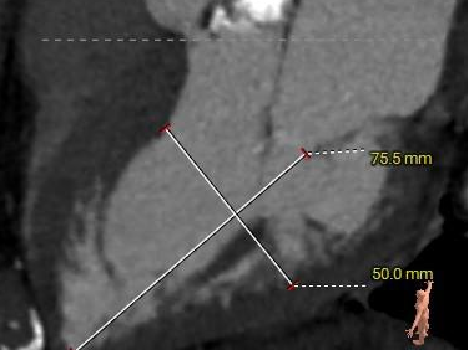

左室测量

外周入路评估

▶ 瓣环水平夹角72°,横位心,主动脉弓角、弓距尚可。

▶ 外周血管内径可,血管走行尚可,右侧股动脉高分叉,左侧股动脉低分叉,腹主动脉见钙化附着。